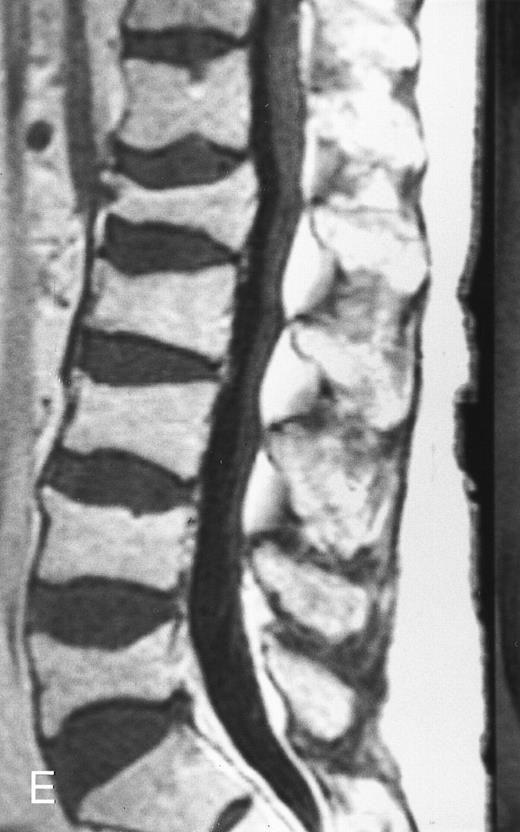

Variegated MR pattern of abnormal marrow in a 45-year-old man with multiple myeloma: T1-weighted (600/20, TR/TE) (A), relatively T2-weighted gradient recalled echo (650/20, TR/TE, flip angle 20°) (B), and enhanced T1-weighted (600/20, TR/TE ) (C) sagittal MR images of the lumbar spine show multiple tiny foci of marrow involvement. Arrows point to island of normal fatty marrow. Sagittal T1-weighted (600/20, TR/TE) MR image 6 months after initiation of chemotherapy (D) shows reappearance of fatty marrow in the spine. Note development of multiple vertebral collapses. T1-weighted MR image 1 year after bone marrow transplantation and total body irradiation (600/20, TR/TE) (E) shows resolution of marrow abnormality and homogeneous bright signal of fatty marrow in the lumbar spine. Note progression of compression fractures. Reprinted with permission from Moulopoulos et al.14,21